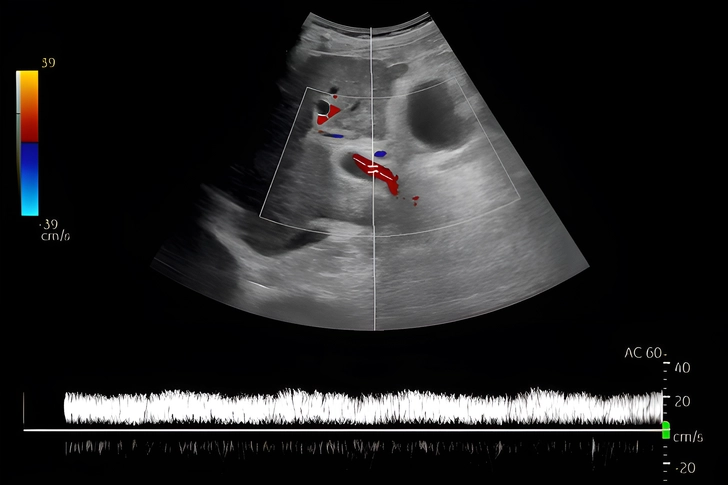

Can an Ultrasound Show Liver Scarring?

Your doctor may have ordered an ultrasound with high-intensity sound waves when you were diagnosed. The image may have showed:

- Extra fat buildup in your liver that was brighter than normal

- Serious liver damage that showed up as lumps or a shrunken liver

You may get a mild, moderate (medium), or serious steatosis (fat) score – a liver fat estimate. But your doctor also checks your FIB-4 score and may order a special type of ultrasound to make sure.

What Is Ultrasound Elastography?

As your condition progresses, ultrasound elastography can estimate your liver fibrosis and stiffness. Using transient and shear waves, the ultrasound bounces sound off your liver which vibrates. But scarred livers are harder, and don't move normally. One common brand, FibroScan, adds a blood test called the enhanced liver fibrosis (ELF) score to estimate your fibrosis risk: